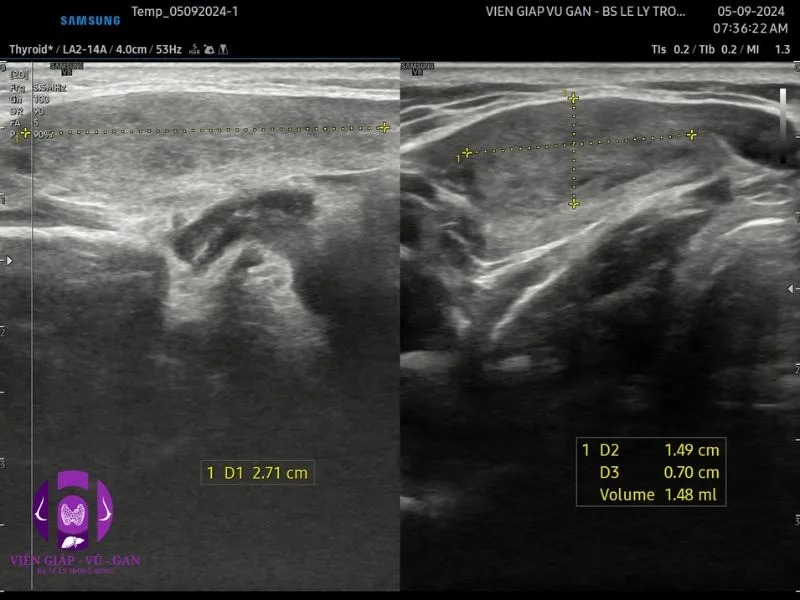

SIÊU ÂM ( máy GE S8 và Sumsung V8 ) ghi nhận :

- Vùng dưới hàm phải, ngay bờ dưới tuyến dưới hàm phải có cấu trúc echo kém không đồng nhất, bờ đều, giới hạn rõ với mô xung quanh, tăng âm phía sau, kt # 20x30mm.

- Doppler cho thấy mạch máu phân bố ngoại vi và trung tâm.

- Kết luận: tổn thương vùng dưới hàm trái nghĩ bướu . Chẩn đoán phân biệt với hạch.